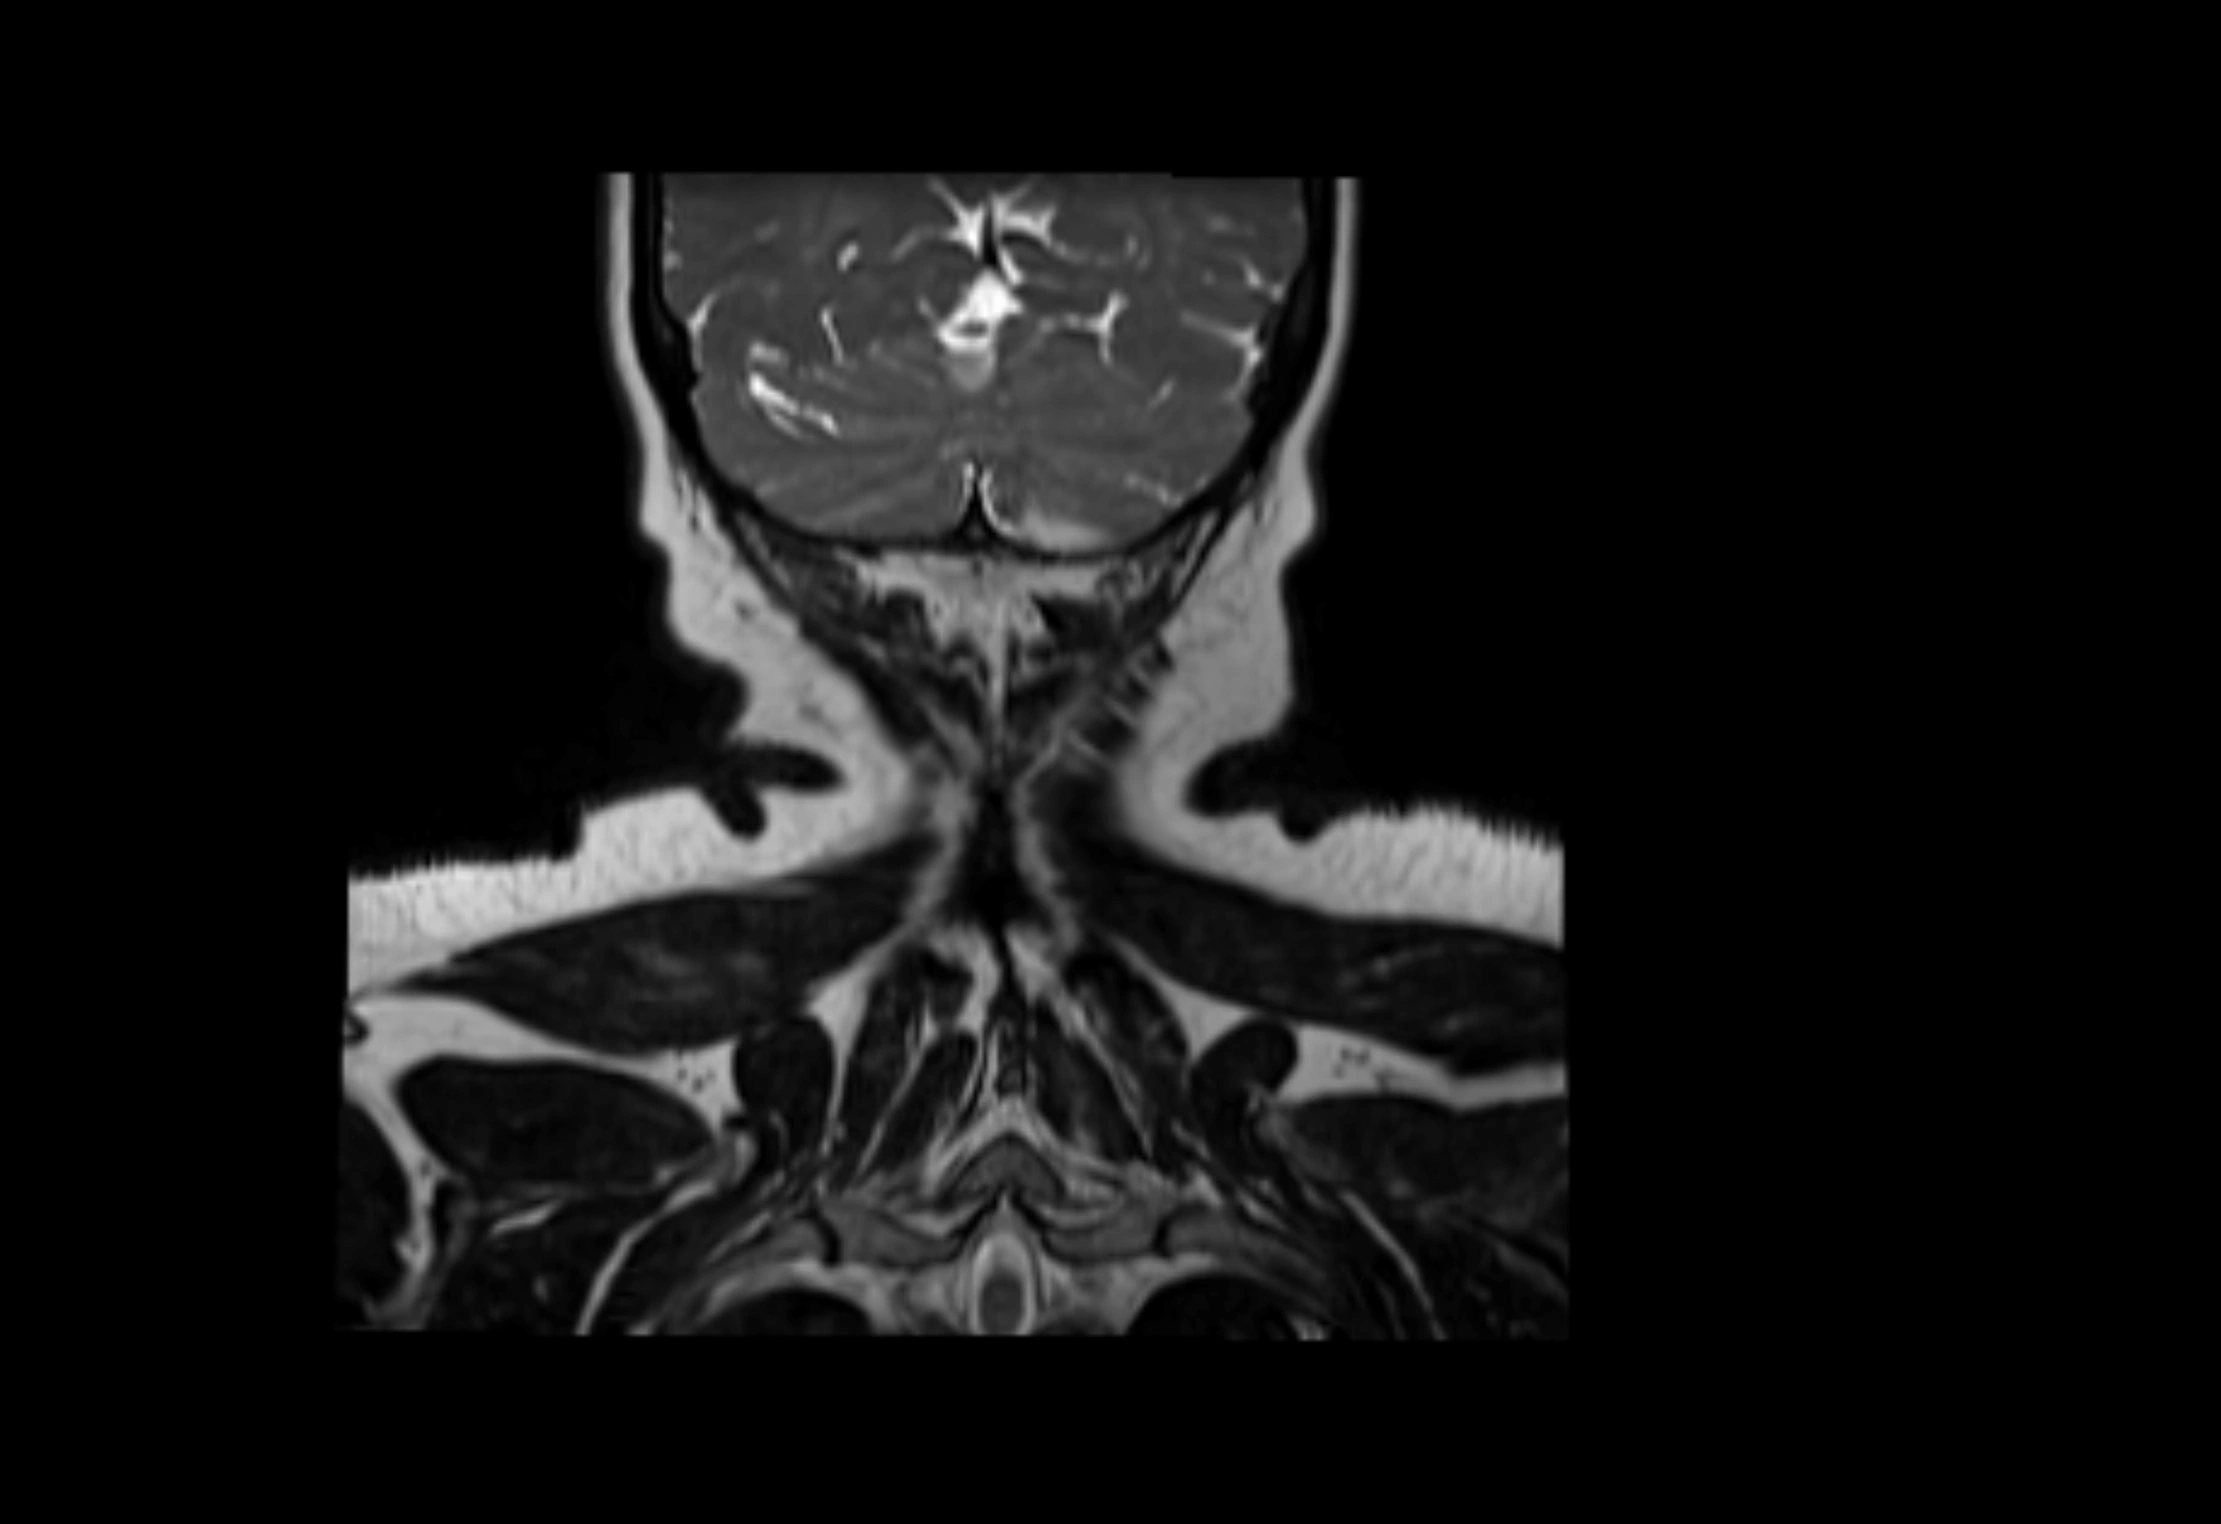

MRI Appearance

T2-weighted images:

• Nodes show intermediate signal, with surrounding fat bright

• Useful for detecting edema, inflammation, or infiltration

• Fatty hilum may appear slightly hyperintense relative to cortex

MRI images

image